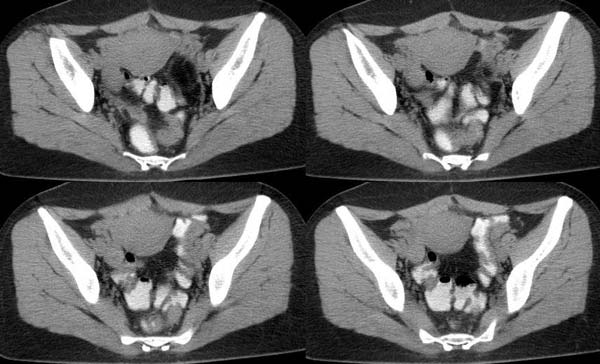

以下是引用守望可可西里在2006-7-25 19:56:00的发言:[br][br] 尽管极象妊娠囊,但“胎儿骨骼12周以后才会在x线片上显影 ,16周以上才可以清晰显示 。一般胎儿的脊柱先出现骨化 ,呈串珠样排列的小点状致密影” 再加上囊内应该是羊水的位置被脂肪密度所取代,还是先考虑畸胎瘤吧。

以下是引用hanlongjiang在2006-7-27 8:24:00的发言:[br]临床手术结果右侧巢畸胎瘤,左侧宫外孕,手术前宫外孕破裂,故手术非常成功,此病例仅凭片子的诊断不能解释其临床表现。想给大家看看,谢谢各位楼主![br]